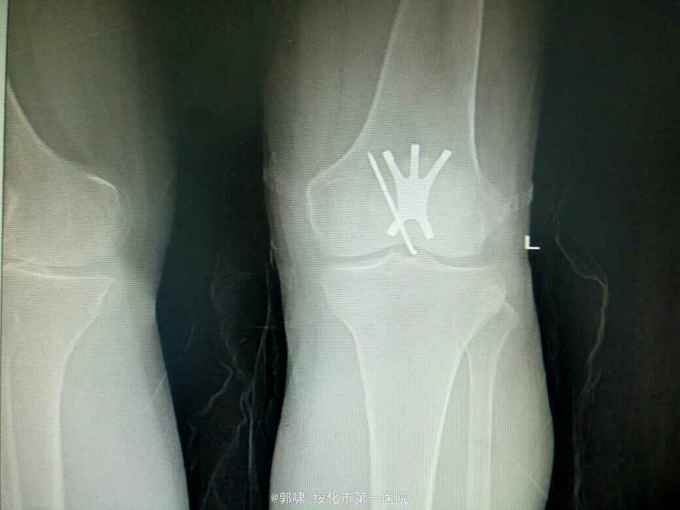

左膝关节摔伤,肿胀,畸形,活动受限一小时。收入院。患者于一小时前滑倒摔伤。当即倒地,左膝关节肿胀,畸形不能行走。门诊拍片示:左膝关节髌骨骨折,断端移位。门诊以左髌骨骨折收入院。

左膝关节肿胀,局部畸形,不能下地行走。浮髌试验阳性。拍片示:左髌骨骨折。

诊断:左髌骨骨折。立即予以腰麻下行切开复位内固定术。术中复位骨折,缝合筋膜,冰水浸泡髌骨爪约10分钟。待髌骨爪变软。选取合适大小的髌骨爪。应用记忆合金髌骨爪内固定。立即用40°温盐水热敷局部。使记忆合金加速抓紧。环抱。缝合爪齿二道,防止脱落。缝合关节囊,韧带组织。术毕。

应用记忆合金髌骨爪内固定髌骨骨折。手术时间基本在20----30分钟内都可以完成。局部损伤小。固定牢靠,确实。患者二个月就可以下地负重活动。具体手术技巧。一是髌骨爪提前用冰盐水侵泡10分钟左右。待记忆合金变软即可使用。二。固定牢靠后立即用40°温盐水热敷。使其快速抓紧。三,缝合爪齿,防脱。四如有粉碎,小的骨块可以缝合筋膜固定。有大骨块,最好环扎钢丝,或穿针固定,有时穿骨隧道钢丝捆扎。效果也不错。只要做到以上几点。安全无忧了!以下是以前做的片子。可以看一看。